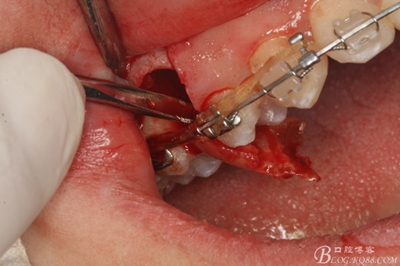

圖15 .微創(chuàng)挺把15牙根縱分成近遠中兩塊

圖16.微創(chuàng)挺挺松近中根面部分,從16與14之間間隙出來

圖17.血管鉗取出近中部分15牙根